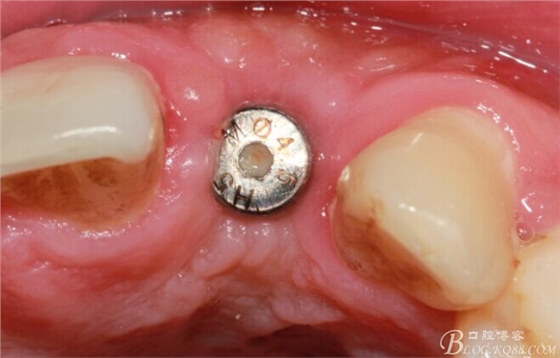

4個(gè)月后,唇側(cè)豐滿度尚可,與鄰牙之間齦乳頭完整。

保留齦乳頭翻小瓣。

翻開后驚喜的發(fā)現(xiàn),術(shù)區(qū)成骨非常好,去除部分骨才暴露那顆長鈦釘。